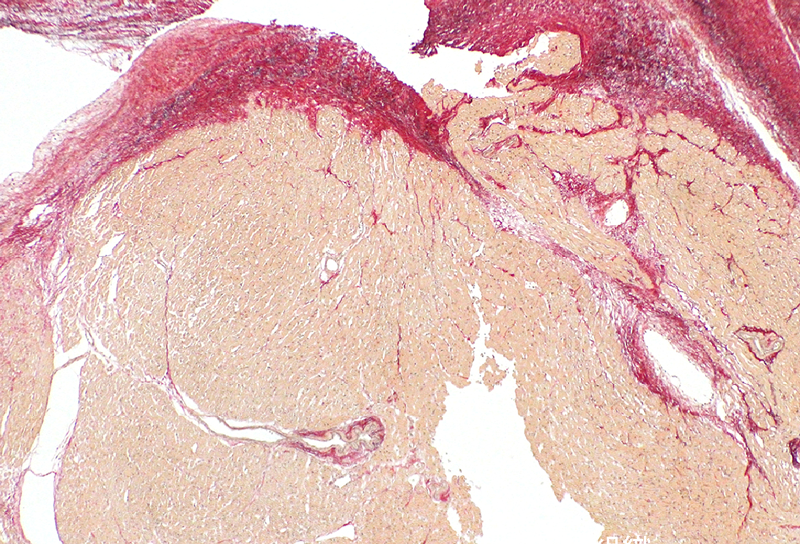

病理所見

隔壁内部は正常心筋組織が主体で,表層は膠原線維に覆われ,一部に弾性線維を認めた.炎症所見は見られず,「正常心内中隔組織」に矛盾しない所見であった(Fig. 4).

Pediatric Cardiology and Cardiac Surgery 32(1): 38-42 (2016)

Fig. 4 Histological findings of the resected partition wall

The partition wall consisted of the myocardium covered with collagen fiber, which was consistent with the normal cardiac septum (Elastica van Gieson stain, original magnification, ×40).

左室二腔症の成因として心筋症からの二次的変化による瘤化3, 4)や,心内膜線維弾性化による収縮能低下,拡張から二腔化を呈する例5),さらには左室心筋の先天的な構築異常から発生する憩室化などが報告されている.これらは先天的素因であるがゆえに胎生期6),あるいは生後すぐに7)異常を指摘される例もあるが,成人期になって発見された報告もあり8)その発症時期は様々である.また,症状や重症度においても心筋梗塞,致死的不整脈,心室破裂など成人期に発症する左室瘤,左室憩室は劇症型であるのに対して9),小児期に発症する二腔症では心雑音や体重増加不良などの緩慢な症状で発症する例が散見され3, 7),その臨床像も多岐にわたる.本症例では乳児期を過ぎて初めて左室内隔壁を指摘され,その後急速に血栓形成,機能低下に至ったという点で過去に例を見ない経過を辿った.胎生期や生直後に形態的異常を認めなかったという点で先天的構築異常に起因する憩室や瘤化は考えにくい.本症例の隔壁組織所見を見ると,膠原線維に覆われた正常心筋組織により構築されていたことから心筋症や緻密化障害などによる形態変化ではないことを示唆している.

術前シンチグフィーにて左室心筋の血流低下を指摘されていたが,後天性虚血変化では通常outpouching形態を呈することが多く,形態的に合致しない.隔壁には僧帽弁乳頭筋が連続しており,その組織像が乳頭筋の発生由来である左室心筋組織10)と相違ないことから,一連の隔壁形成過程が何らかの乳頭筋,左室心筋の構造変化に関与しているものと考えられる.左室副腔壁組織が肥厚した心筋と膠原線維から成るという組織学的に近似した報告例がある11)ものの二腔化成因については言及されておらず,隔壁の形成過程を正確に把握することは極めて困難である.